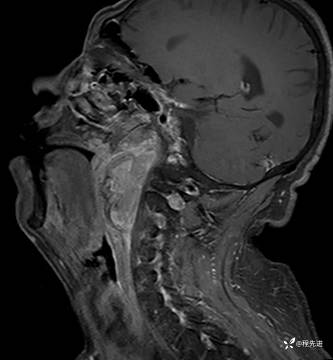

【面颈】特别精彩病例|呼吸费力3月余,声嘶2月余,左侧鼻咽部占位期待您的精彩解读

患者性别:男

患者年龄:58岁

主诉:呼吸费力3月余,声嘶2月余

现病史:患者3月前劳作后出现呼吸费力,胸闷气促。外院颈部CT检查提示:左侧颈部肿物。3月来颈部肿物逐渐增大,劳作后呼吸困难加重;2月前出现声音嘶哑,逐渐加重。现患者至我院门诊就诊,拟“左侧咽旁间隙良性肿瘤”收住入院

MRI平扫+增强:

T1增强: